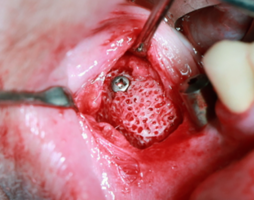

В момент оперативного вмешательства хирургу необходимо только провести позиционирование аллогенного имплантата, и фиксацию его с помощью титановых мини-винтов (рис.3).

Благодаря соответствию аллогенного имплантата форме принимаемого костного участка нижней челюсти, планируемого к последующей дентальной имплантации, у всех пациентов была достигнута первичная стабильность перед фиксацией мини-винтами.

У второй группы пациентов расстояние между кортикальной пластинкой альвеолярной части нижней челюсти и индивидуальным аллогенным имплантатом составляло 0,1 - 0,4 мм, рис. 6.